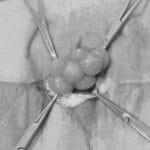

当院はウサギ・小動物・爬虫類・鳥類などのエキゾチックアニマル専門の病院です。

エキゾチックアニマルの診療

専門的なエキゾチックアニマル診療を提供しています。爬虫類、鳥類、小動物など、幅広い種類に対応。専門知識と経験を活かしたケアを提供。